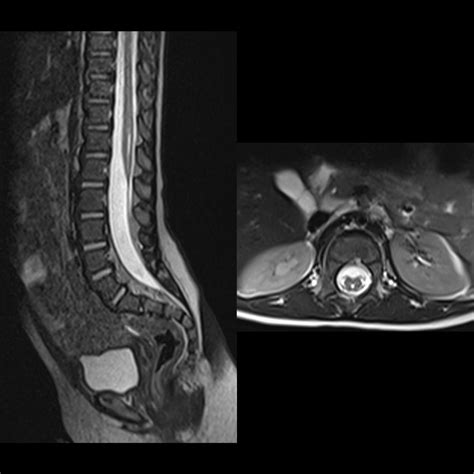

If the ultrasound shows anything unusual, such as a low-lying spinal cord or a tethered cord (where the spinal cord is pulled downward), further imaging, such as an MRI, may be ordered. An MRI provides a more detailed picture of the spinal cord structures and is usually performed if there is a strong suspicion of an abnormality that needs potential surgical management.